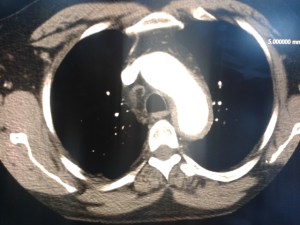

aorta2